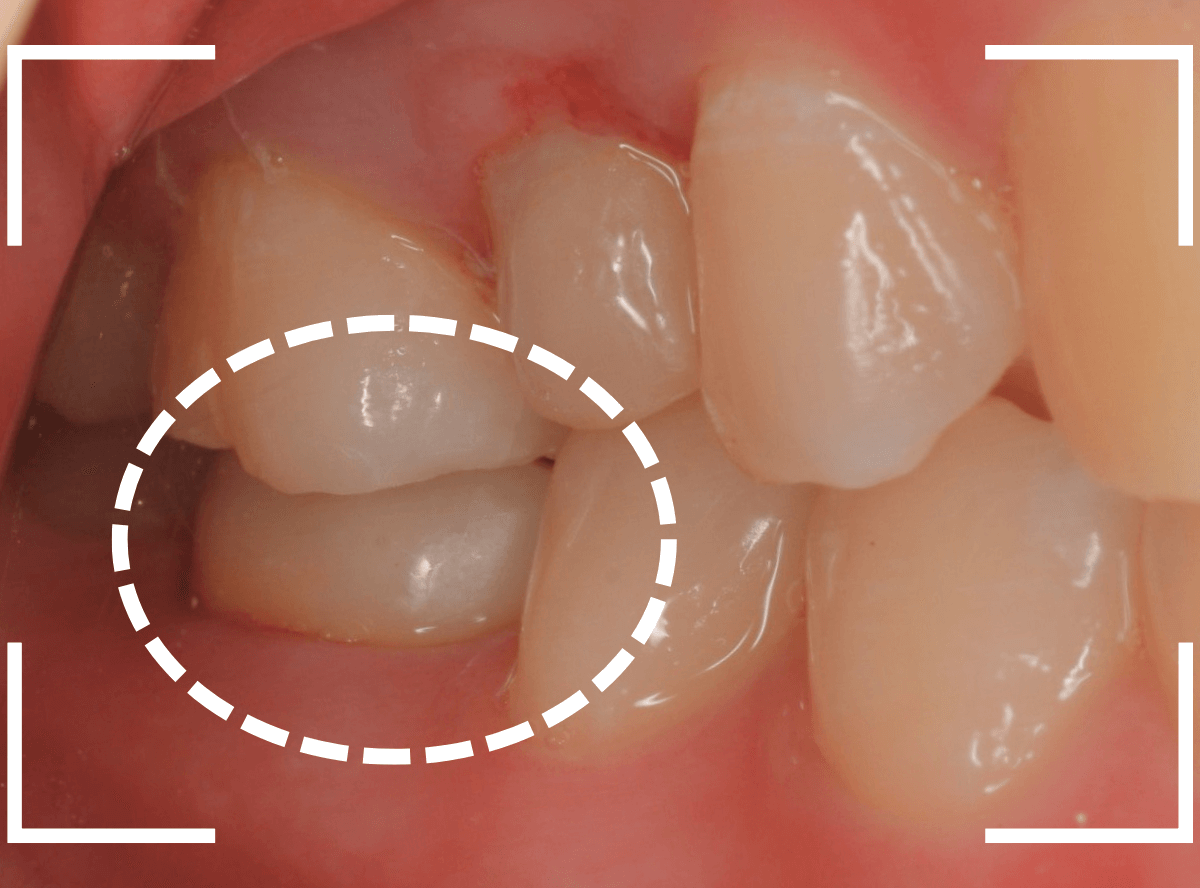

さし歯を入れるスペースがない!

一番奥の歯が土台(コア)の治療までで中断してしまってる患者さんの例です。

本来であれば、この上にさし歯を作らなければいけないのですが、この時点でかみ合ってしまい、さし歯を作ろうにも作りづらい状況でうやむやのうちに治療中断になってしまったようです。

まず、土台の治療をしてから時間が経過していることと、不適合になっている事から、外して中を調べます。

すると、土台の中で虫歯にもなっていました。

(〇部の赤い部分)

こういった事は、レントゲン写真でもよくわからない事が多く、土台を外す治療は本当に神経を使います。